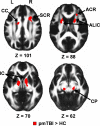

Whole-brain voxelwise results for visit 1 data, presented on an average FA template in Montreal Neurological Institute space (axial slice locations = Z). Selected regions showing increased FA for the pmTBI patients relative to the matched HC included the CC, ACR, SCR, anterior limb of the internal capsule (ALIC), IC, and CP. L, Left; R, right.